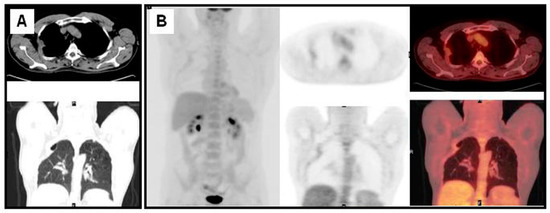

Figure 4.

Patient with a NSCLC in the left superior lobe treated three years before with chemo-radiotherapy. A radiological exam showed sclerotic bone lesions (A); FDG PET/CT showed multiple bone, left supraclavicular lymph nodes and lung metastases (B).